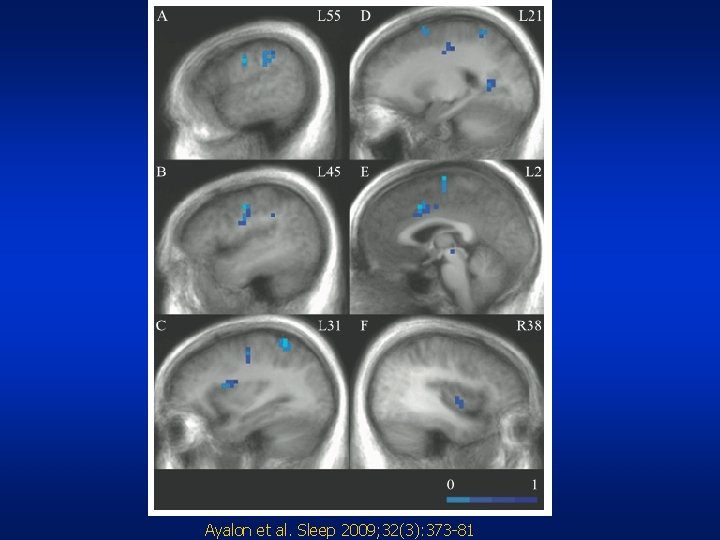

OSA reduces brain activation • Sustained attention task • f. MRI imaging • Precentral gyrus, insula, parietal lobe, cingulate gyrus, affected Ayalon et al. Sleep 2009; 32(3): 373 -81

Ayalon et al. Sleep 2009; 32(3): 373 -81